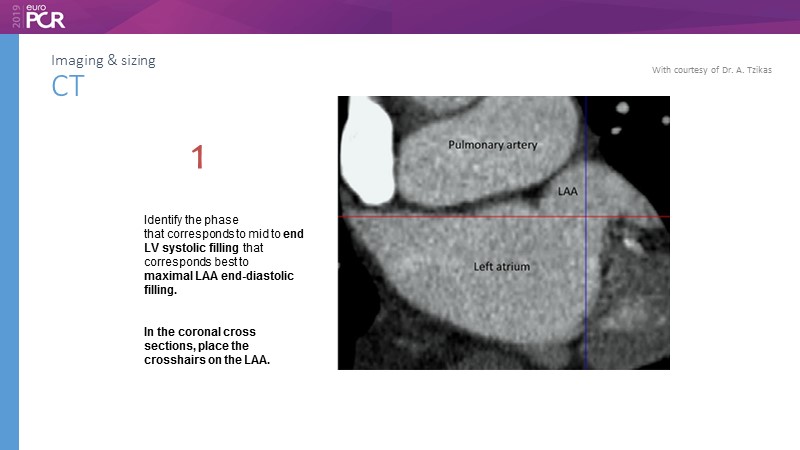

I. Cruz-Gonzalez

Pre-procedure planning